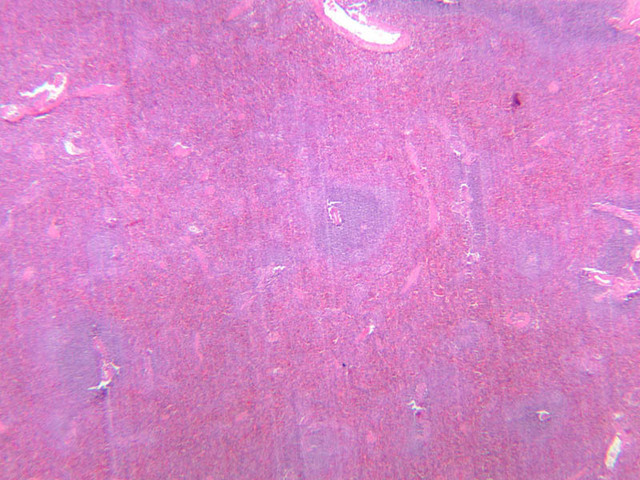

Another encapsulated lymphoid organ is the thymus. In the developing animal, this tissue contains the most important concentration of lymphocytes in the body. If the thymus is removed, lymphoid nodular tissue elsewhere does not develop properly and the ability of the animal to develop immunological competence is impaired. In a newborn or young animal, therefore, the thymus is a large lymphoid structure. After maturity the thymus undergoes involution, although some of the structural features persist and will be found embedded in fatty tissue.

Examine slides A-43 through A-46 (A-43, H&E [2.5x, 10x, 20x]; A-44, H&E [10x, 20x, 40x]; A-46, H&E [2.5x-labeled, 10x, 20x-labeled, 40x]). Slides A-44 and [[http://www.medicalhistology.us/wiki/bin/viewfile/Main/ThymusImages?rev=1;filename=a45_hassall_corpuscle_medulla_infant_thymus_2x.jpg][A- 45]] are from infants and slide A-46 is from a young adolescent. Compare slide A-43 (adult thymus) to slide A-44 (infant thymus). First hold the slides up to the light and observe by eye that there is an increase in the amount of CT (and fat) that infiltrates the tissue with age. Now observe the differences in the appearance of the tissue at the microscopic level. Like the lymph node and spleen, the thymus is encapsulated, and the capsular connective tissue penetrates into the lymphoid tissue dividing it into compartments. But only the thymus appears lobulated. Each lobule is divided into a darker staining peripheral cortex and a lighter staining medulla. Diagnostic of the thymus are Hassall's corpuscles (A-45 [2.5x, 10x, 20x, 40x-labeled]). These are concentrically layered, eosinophilic structures found in the medulla.

Examine a section of young thymus (slides A-44, A-45). Note that it is surrounded by a thin CT capsule. Trabeculae from the capsule pass into the organ to divide the thymus incompletely into lobes (separated by thick trabeculae) and lobules (separated by thinner trabeculae). Notice that the lobules and lobes join centrally, making the parenchyma of the organ continuous throughout. Each lobule shows an outer, cortical region, densely packed with cells that are mostly lymphocytes, and a core or medullary region containing fewer cells. Lymphoid nodules with their germinal centers are absent from the thymus because it has no afferent lymphatics, i.e. this organ does not filter lymph. Examine the cortex and find large and small lymphocytes (A-44, H&E [2.5x, 10x, 20x, 40x] [2.5x, 10x, 20x, 40x]; A-45, H&E [10x, 20x, 40x] [2.5x, 10x, 20x, 40x] [2.5x, 10x, 20x, 40x]). Look for mitotic figures in the thymic cortex; these are lymphoblasts. Also try to discern large cells with acidophilic cytoplasm and large nuclei interspersed among the lymphocytes. These are the epithelioreticular cells. Now look at the medullary region where lymphocytes are sparser (A-44, H&E [10x, 20x, 40x]; A-45, H&E [2.5x, 10x, 20x, 40x-labeled] [10x, 20x, 40x]). Epithelioreticular cells are more readily apparent. Unlike the reticular cells in other lymphatic organs which are of mesenchymal descent, these reticular cells arise from epithelium of the pharyngeal pouches. Like other epithelial cells, thymic reticular cells are joined by desmosomes. In the thymus, the epithelioreticular cells form a cellular reticulum that supports the thymocytes.

Scattered randomly in the medullary tissue are acidophilic structures whose cells are concentrically arranged around an amorphous core. These are the thymic or Hassall's corpuscles. Hassall's corpuscles vary in size and appearance and are comprised of degenerated reticular cells that contain keratohyalin granules and keratin. No known function has been assigned to them.